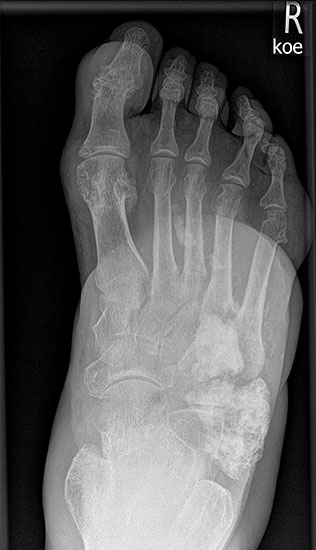

Das solitäre Enchondrom ist von Enchondromatosen, also disseminierten Enchondromen der Extremitäten und des Achsskeletts, abzugrenzen. Die Entartungswahrscheinlichkeit ist für Enchondromatosen wie dem M. Ollier (Abb. 18a und b) oder dem Maffuci-Syndrom deutlich erhöht und wird in der Literatur bis zu 25% angegeben. Klinische und radiologische Hinwiese für eine Entartung beinhalten Kortikalisveränderungen, wie -verdickung, -destruktion und die enossale Kortikalisarrosion, welche in der CT-Bildgebung mehr als 2/3 der Zirkumferenz des betroffenen (Röhren-) Knochens umfasst.

Das primäre, konventionelle Chondrosarkom des Fußes, welches nicht sekundär aus einem Enchondrom oder einer Exostose (exophytäres bzw. exostotisches Chondroarkom) sondern de novo entsteht, zeigt, ähnlich wie das Enchondrom, eine Prädilektion für die kurzen Röhren­knochen (Abb. 19). Das durchschnittliche Alter liegt hier bei 52 Jahren mit einer Bevorzugung des männlichen Geschlechts. In Abhängigkeit der Lokalisation und Graduierung des Tumors umfasst die geeignete operative Therapie die intraläsionale Curettage (G1) bis hin zur Amputation (G3) 34. Das Chondrosarkom ist nicht Strahlen- oder Chemotherapie-sensibel. Eine vollständige chirurgische Resektion bleibt deshalb die einzig sinnvolle Therapiemöglichkeit.